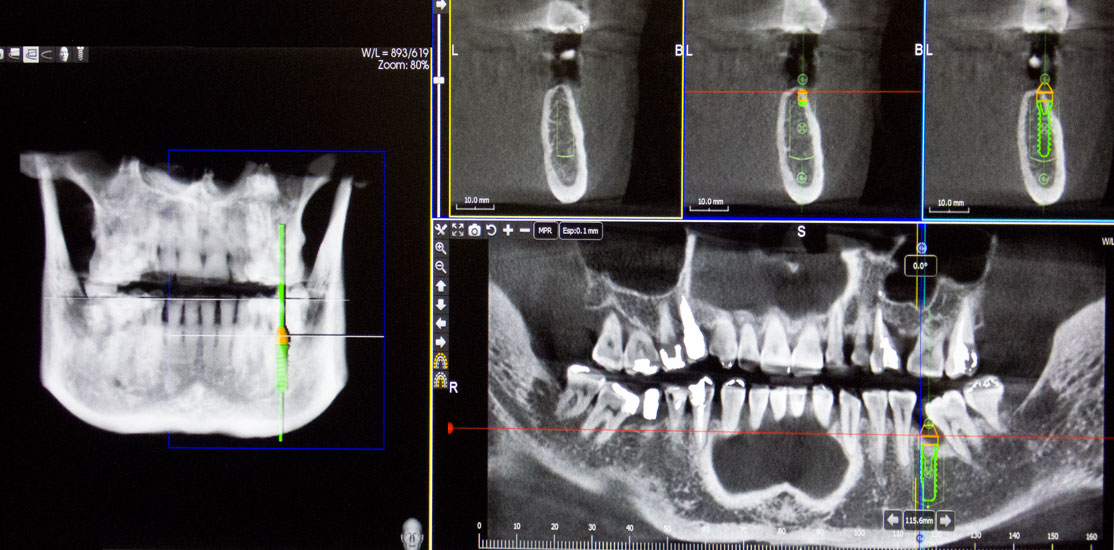

La clínica dental Osagest, en su continuo afán de mejorar la calidad de sus tratamientos e incorporando siempre las últimas novedades en tecnología de vanguardia, ha entrado de lleno en el proceso de digitalización tecnológica con la adquisición de un Scaner 3D de última generación.

Con este Scaner obtenemos imágenes tridimensionales de la región bucofacial, dientes, hueso maxilar y mandibular, zona sinusal, etc.,  permitiéndonos evaluar con gran precisión el estado del paciente que acude a nuestra consulta, realizando un diagnóstico preciso, que nos posibilita estructurar el mejor tratamiento en cada circunstancia, evitando falsas expectativas y la frustración que conlleva el fracaso de tratamientos inadecuados por su errónea planificación.

La información  aportada por la tecnología 3D nos permite la realización de técnicas innovadoras de regeneración ósea guiada con coágulo del propio paciente, en zonas de gran pérdida de hueso, produciendo resultados altamente predecibles que nos facilitan restaurar la función masticatoria y estética, que los tratamientos convencionales no consiguen.

Las imágenes obtenidas mediante tecnología 3D, nos aportan información fiable de la zona bucodental que requiere tratamiento quirúrgico o conservador, minimizando en gran medida las complicaciones que pueden producirse si no disponemos de ella.